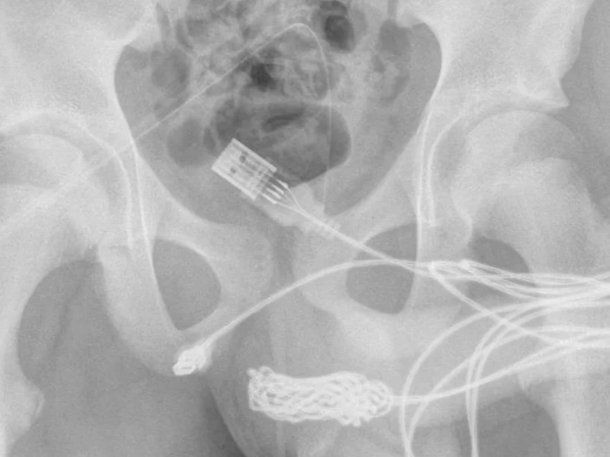

“Se descubrió que los dos puertos distales del cable USB sobresalían del meato uretral externo, mientras que la parte media del cable anudado permanecía dentro de la uretra”, indicaron los médicos en un informe difundido por ScienceDirect.com.

Durante la cirugía para extraer el cable que tenía atrapado el joven en su pene, los médicos realizaron una inserción entre los genitales y el ano. De esa forma, lograron acceder al USB mediante los catéteres que habían colocado.

"Se realizó una incisión penoescrotal longitudinal sobre el cuerpo extraño palpable y se realizó una disección cuidadosa a través de los tejidos más profundos, dividiendo el músculo bulboesponjoso", detallaron los expertos sobre el procedimiento insólito. Allí también destacaron que “ambos extremos del cable se sacaron con éxito a través del meato uretral externo”.